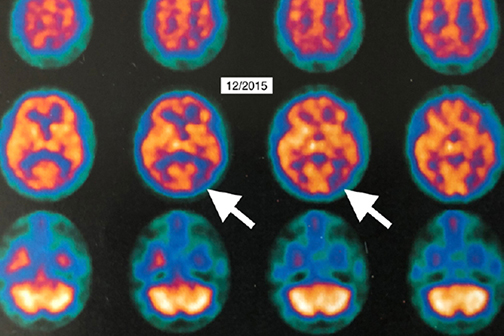

LSU Health New Orleans Discovers Major Contributor to Alzheimer’s Disease

Research led by Drs. Yuhai Zhao and Walter J Lukiw at the LSU Health New Orleans Neuroscience Center and the Departments of Cell Biology and Anatomy, Neurology and Ophthalmology, reports for the first time a pathway that begins in the gut and ends with a potent pro-inflammatory toxin in brain cells contributing to the development of Alzheimer’s disease (AD). They also report a simple way to prevent it. More